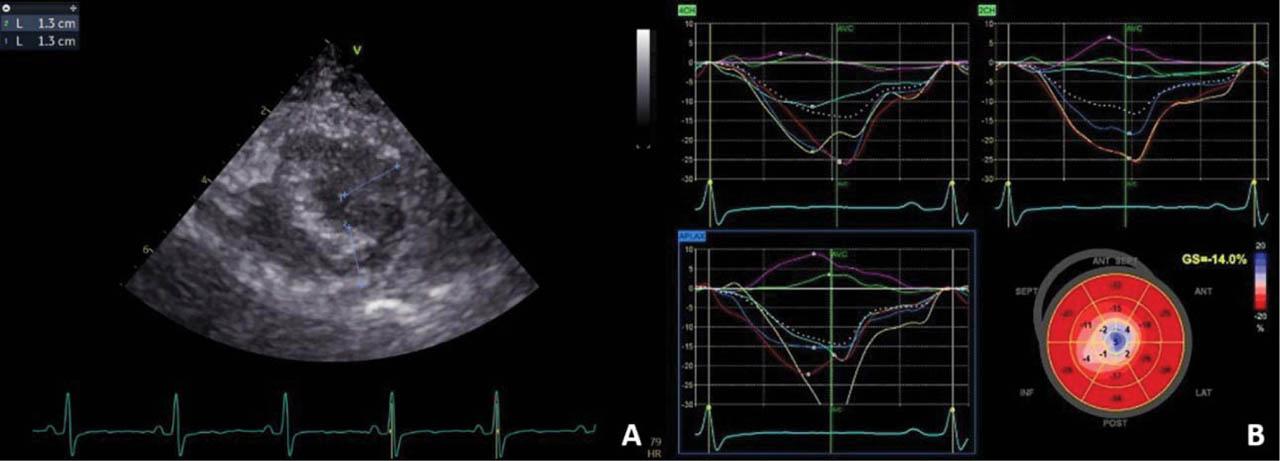

Figure 5

(A) Transthoracic echocardiography, short-axis view of the apex, 2D examination: left ventricular apical hypertrophy. (B) Transthoracic 2D speckle-tracking echocardiography: paradoxical strain of the left ventricular apex suggestive of hypertrophic cardiomyopathy.